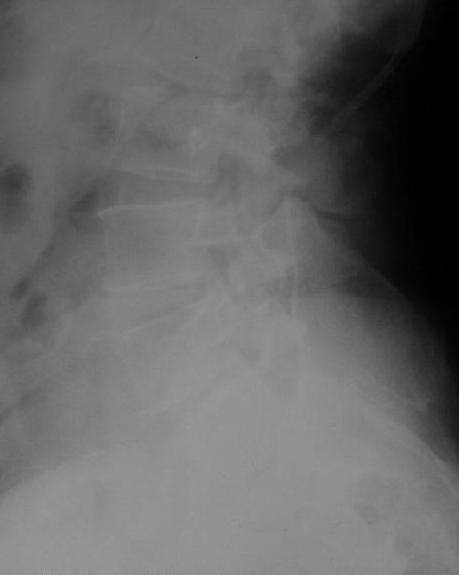

У больной 53 лет в последний год появились сильные боли в пояснице.

При обследовании выявлен анкилоз тазобедренного сустава в приведении. Видимо, в период пребывания в тяжелом состоянии появились гетеротопические оссификаты. За исключением того, что осталась одна почка, сейчас других медицинских проблем нет.

Пациентку в первую очередь беспокоят боли в спине, на отсутствие движений в суставе она вроде и не жалуется. Вопрос насчет тактики. Корсет и анальгетики вряд ли решение. Первый вариант - удаление оссификатов и эндпротезирование, второй - корригирующая остеотомия в проксимальном отделе с устранением порочного положения.

Крайне желательно выполнить МРТ поясничного отдела, так как на представленных рентгенограммах складывается впечатление о спондилолистезе L5,котрый наиболее вероятно и является причной болевого синдрома. Кроме того у болной имеется высокий риск гнойного поражения позвоночника. Только после МРТ можно планировать коррекцию вторичной деформации позвоночника.

Снимок поясничного отдела плохо просматривается на моем компе. Нет ли там спондилолистеза L5-S1?

Учитывая отсутствие жалоб со стороны тазобедренного сустава - оперативое лечение вряд ли принесет позитивный результат. На первый план выступает спондилолизный спондилолистез (вниматльно посмотрите снимки поясничного отдела)L5 позвонка. На наш взляд больному рекомндовано выполнить транспедикулярную коррекцию и фиксацию сегментов L4-S1 с установкой кейджа в L5-S1.